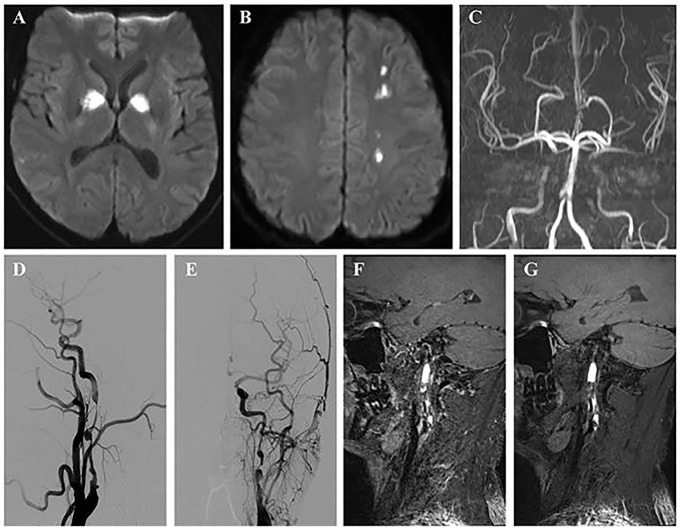

A case of spontaneous bilateral internal carotid artery dissection (ICAD) in a 36-year-old male, potentially linked to COVID-19, is reported. Initially presenting with excessive daytime sleepiness, an atypical symptom for ICAD, the patient lacked focal neurologic deficits. Diagnostic evaluation revealed severe stenosis and dissecting aneurysms in both carotid arteries. Treatment included anticoagulation, corticosteroid therapy, and subsequent endovascular stent placement. This case underscores the importance of considering ICAD as a potential complication of COVID-19, especially in patients with atypical symptoms. Further research is needed to understand the underlying mechanisms and optimize treatment strategies.

Abstract Image